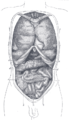

التشريح

الجزء | الأصل |

sternal | two fleshy slips from the back of the xiphoid process. |

costal | the inner surfaces of the cartilages and adjacent portions of the lower six ribs on either side, interdigitating with the Transversus abdominis. |

lumbar | aponeurotic arches, named the lumbocostal arches, and from the lumbar vertebrae by two pillars or crura. |